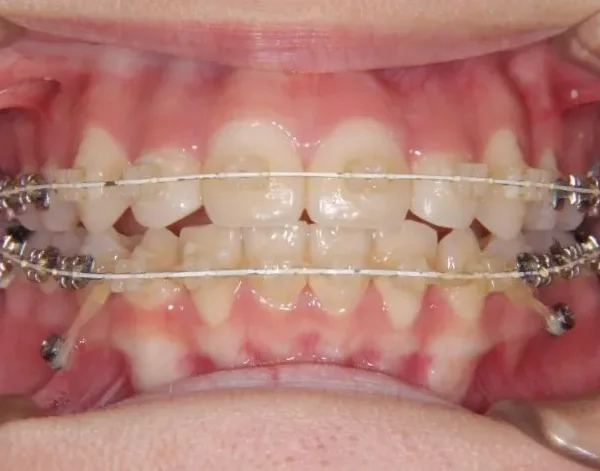

• 治療経過1

治療経過1

歯科矯正アンカースクリューを用いた治療で、非抜歯で口唇突出の改善、臼歯の圧下、叢生の解消を図りました。

診断名 叢生・開咬・上下顎前突 装置名

マルチブラケット装置

歯科矯正用アンカースクリュー